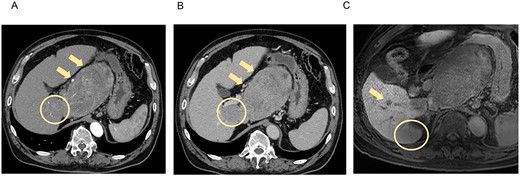

A 66-year-old man presented to his previous doctor with abdominal pain. He had a medical history of hepatitis C for which he had achieved a sustained virological response with direct-acting antivirals 5 years ago. Laboratory findings showed increased concentrations of alpha-fetoprotein (AFP; 31 ng/mL) and protein induced by vitamin K absence or antagonist-II (PIVKA-II; 75 528 ng/mL), and normal liver function (Child-Pugh class A, liver damage classification A, and albumin-bilirubin index −2.87). Computed tomography (CT) and magnetic resonance imaging (MRI) at the initial examination revealed four mass lesions: a 14-cm-diameter and 3-cm-diameter lesion in segment 1 (S1), a 5-cm-diameter lesion in S6/7, and a 1-cm-diameter lesion in S6 (Fig. 1).

CT and MRI at the initial examination. Axial enhanced CT reveals mass lesions of 14 cm (A, B, arrow) and 3 cm (A, B, circle) in S1, with heterogenous enhancement in the arterial phase (A) and a washout pattern in the portal phase (B). Axial enhanced MRI shows the lesions in S1 and other lesions of 5 cm in S6/7 (C, circle) and 1 cm in S6 (C, arrow), which demonstrate decreased ethoxybenzyl uptake. S, segment.